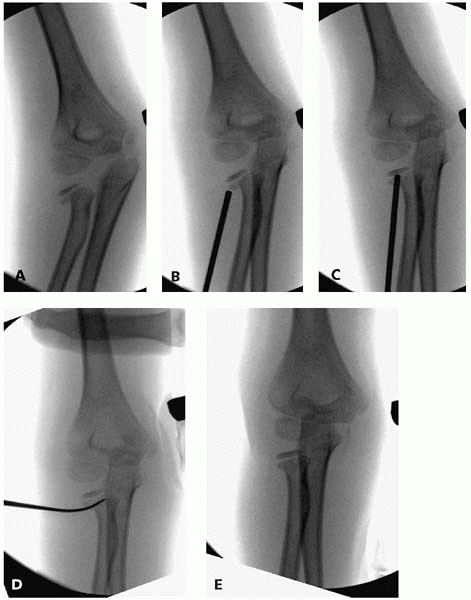

![]() |

|

▪ FIGURE 6-8 A: Anterior-posterior radiograph demonstrating the horizontal pin failing to engage ossific bone in the proximal to the fracture. B: Ten weeks following surgery, the patient has elbow pain and stiffness, and the radiograph demonstrates a lack of union. C:

Rigid fixation with a compression screw was used at time of second surgery to allow early motion. Screw should be only in the lateral column and not in the olecranon fossa or terminal elbow extension would be compromised. D: Preferable pin configuration. Both cortices in the proximal fragment are engaged. Pins are not in the olecranon, allowing for early motion with full extension if desired. E: Lateral view showing the proximal pin exiting through the posterior cortex. This is common as the capitellum is an anterior structure, so pins may have an anterior to posterior direction. |

the distal fragment and makes the reduction much easier. Two smooth

pins are placed percutaneously just posterior to the incision in a

parallel or divergent manner, and fixation stability is assessed. A

potential pitfall is having the more distal K-wire wholly in epiphyseal

cartilage, failing to engage cortex (Fig. 6-8).